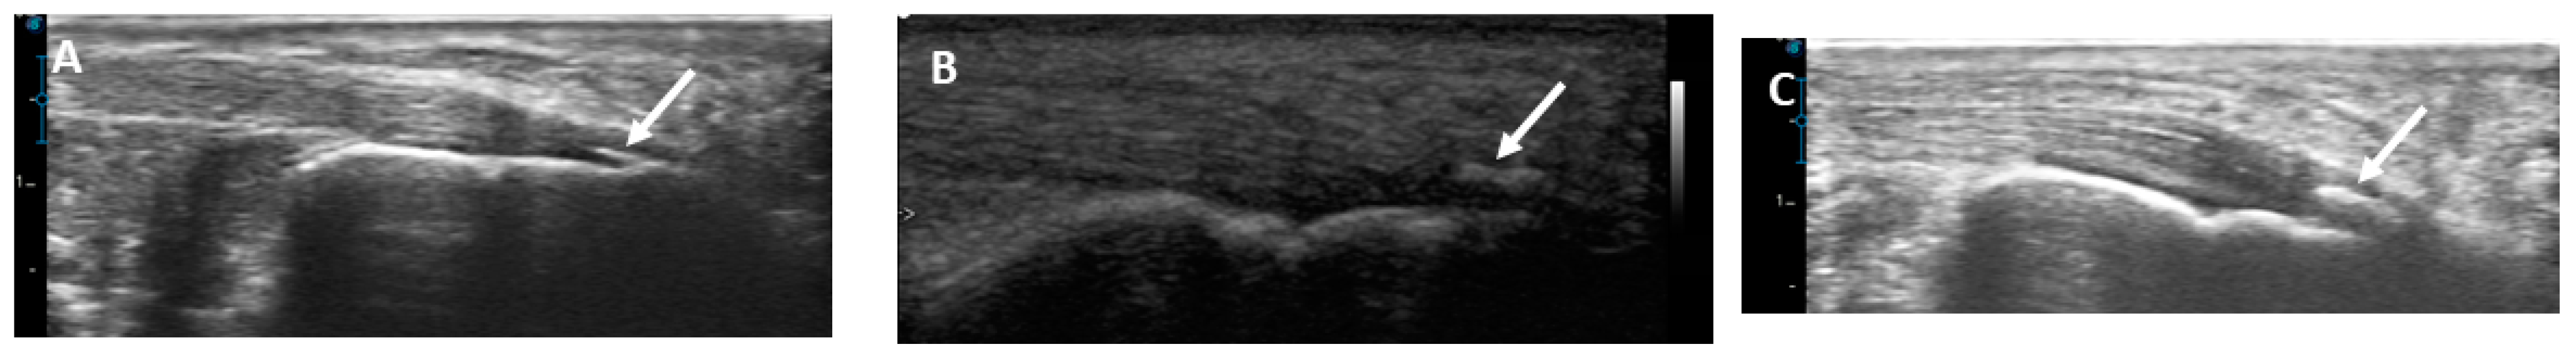

2.4. Musculoskeletal Ultrasound of the Achilles Tendon